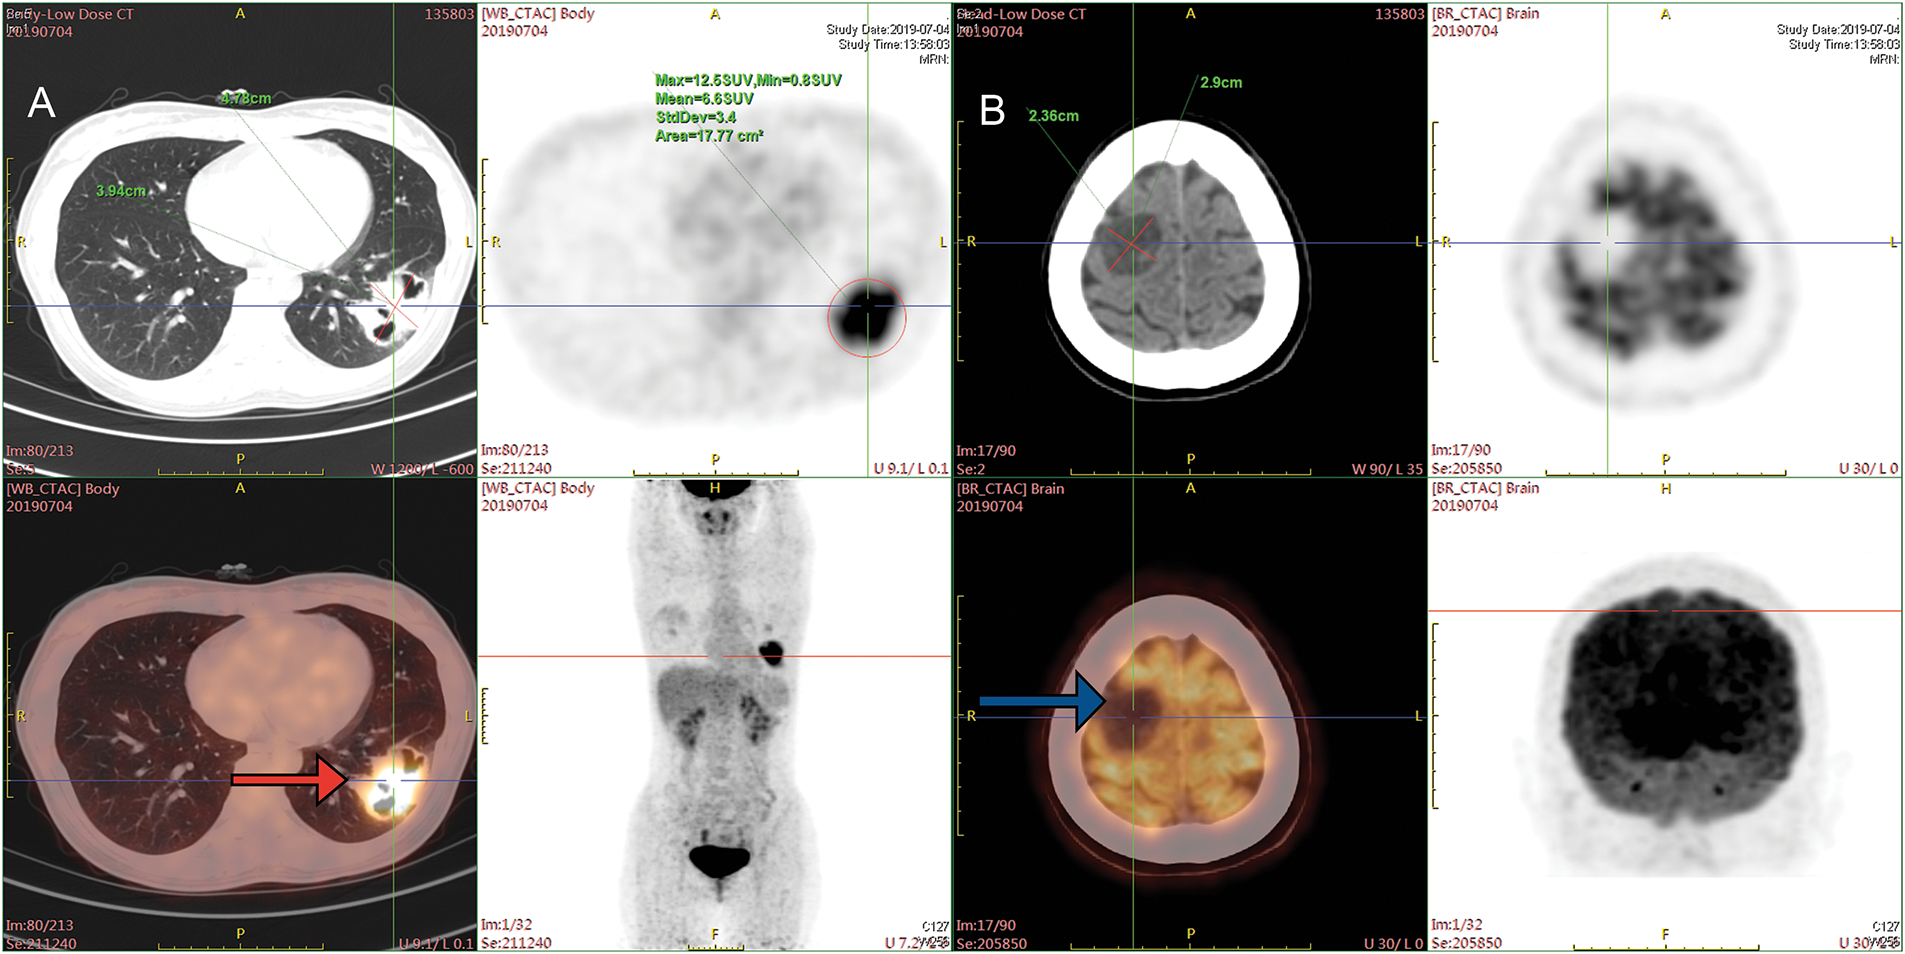

A 33-year-old female presenting with a persistent cough and sputum containing dark red blood was admitted to Xinqiao Hospital of Army Medical University on 02 July 2019. She was a non-smoker and had no medical history. Upon admission, a physical examination was performed and revealed no significant abnormalities. Enhanced chest computed tomography (CT) revealed a mass in the lower lobe of the left lung, with a longest diameter of about 4.9 cm. Enhanced cranial magnetic resonance imaging (MRI) showed a tumor in the right parietal region, with a longest diameter of about 3.0 cm, which was considered suspicious for metastasis. Positron emission tomography-computed tomography (PET-CT) findings were consistent with these results (Fig. 1A,B). The patient underwent ultrasound-guided lung biopsy. The pathological result confirmed left lower lobe pulmonary lymphoepithelioma-like carcinoma, with immunohistochemistry showing P63+, P40+, Ki-67 50%, TTF-1-, NAPSINA-, SYN-, vimentin focal+. In situ, hybridization showed EBER+. No mutations or fusions were detected in EGFR, ROS1, RAS/RAF, or PIK3CA. Further examinations, including nasopharyngeal MRI and nasopharyngoscopy, showed no abnormalities. Based on the above examinations, the patient has been formally diagnosed with stage IVa lymphoepithelioma-like carcinoma of the left lower lung (cT2bN0M1b). We initiated an MDT discussion; at that time, both neurosurgeons and thoracic surgeons considered that this patient had no clear indication for surgery. In accordance with the NCCN guidelines and the patient’s wishes, she received seven cycles of nab-paclitaxel and toripalimab combination therapy, achieving stable disease (SD), followed by maintenance therapy with toripalimab.

Figure 1: PET-CT images at the time of initial diagnosis. (A) PET-CT on 04 July 2019, before treatment. The mass at the peripheral basal segment of the left lower lobe showed increased FDG uptake (red arrow). (B) Low-density lesions in the right parietal lobe, with increased FDG metabolism (blue arrow). PET-CT = Positron emission tomography-computed tomography, FDG = fluorodeoxyglucose